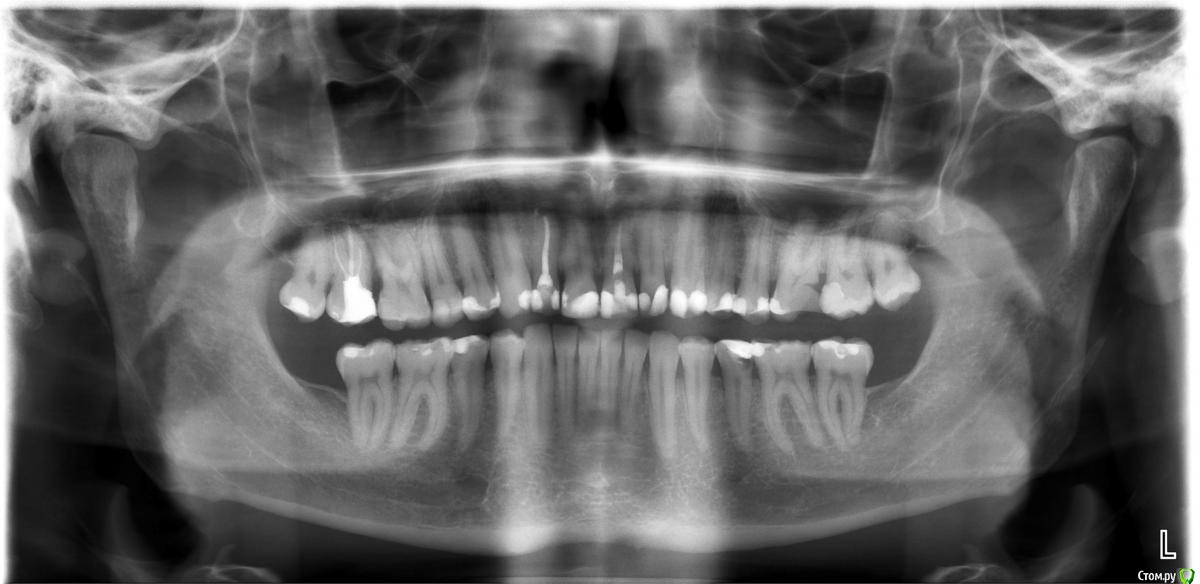

Tym Опубликовано 3 февраля, 2020 Поделиться Опубликовано 3 февраля, 2020 Здравствуйте, уважаемые специалисты!Вожно ли сохранить 7 и 6 верхние зубы (избежать удаления?), при очаговой, незначительной резорбции костной ткани в области 7 и 6 зубов, возникшей в результате хронического воспаления, являющегося следствием глубокого зубодесневого (костного) кармана между 7 и 6 зубами? Сопутствующие факторы: пародонтит, уплощение слизистой гайморовой пазухи.Фотографии КТ-снимков (сделаны с монитора ПК) прилагаю.Можете ли кто помочь в лечении данных зубов без удаления? Ссылка на комментарий

chervoncevdaniil Опубликовано 4 февраля, 2020 Поделиться Опубликовано 4 февраля, 2020 По этому снимку показаний для удаления я не вижу Ссылка на комментарий

ЛанаМ Опубликовано 4 февраля, 2020 Поделиться Опубликовано 4 февраля, 2020 Проблема решаема. Сначала заменить пломбы на проблемных зубах, восстановить контактные пункты, 17 зуб - одеть коронку, 26 и 27 возможно потребуется эндолечение с последующим протезированием. Точно сказать можно при очном осмотре. Далее наблюдение у паролонтолога. Когда пища перестанет набиваться в межзубные промежутки, то и воспалительный процесс уменьшится. Ссылка на комментарий